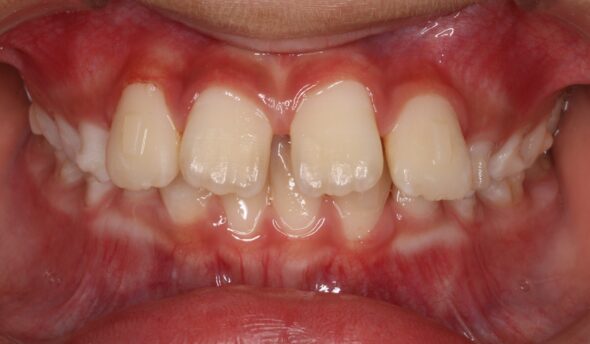

矯正術前:正面

今回ご紹介する患者様は、下の前歯のがたつきを気にされており、矯正検査後叢生Ⅰ級と診断いたしました。

| 治療内容 | 患者様は、下の前歯のがたつきを気にされており、矯正検査後叢生Ⅰ級と診断いたしました |